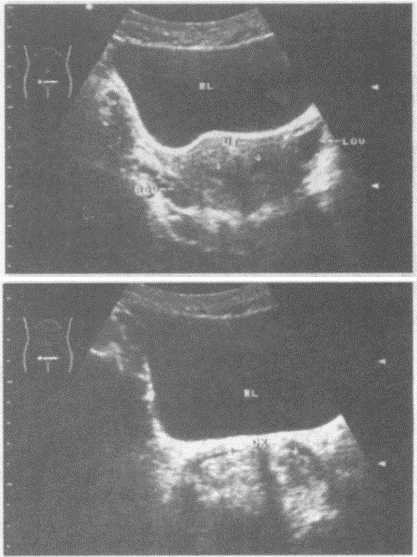

再说说细节,产科远程超声技术操作起来简单得很,社区护士或家人帮忙摆弄设备就行,医生远程操控探头方向,图像清晰得连宝宝的小手指都能瞅见。过程中,孕妈可以放松躺着,听听音乐聊聊天,不像在医院那么紧张。有一次,我陪表妹做检查,她一开始还嘀咕“这能行吗”,结果看到屏幕里宝宝在踢腿,医生实时解说“宝宝活泼健康”,她眼泪都掉下来了——那是安心的泪啊!这种技术不仅缓解了孕妈的心理压力,还减少了交叉感染的风险,毕竟少去人多嘴杂的医院,对母婴都是保护。您想啊,孕期情绪波动大,这种便捷方式让妈妈们更舒心,宝宝也能在肚子里更安稳地成长。